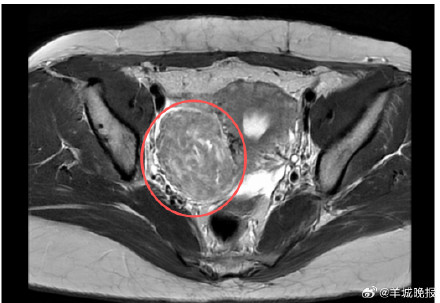

近日,来自广州的吴女士突然出现月经量增多、腰痛、尿频等现象,来到广医三院检查后发现,最大的子宫肌瘤已经堪比成年男性拳头大小,并长在了子宫旁的阔韧带上,长此以往可能影响肾功能。原来,吴女士八年前就已查出子宫肌瘤,但因无症状所以并未留意。医院妇科主任刘娟提醒,子宫肌瘤虽然是一种恶变概率不高的良性肿瘤,并非所有都需要手术,但仍需定期复查,若身体出现上述症状后需及时介入治疗。(记者:王沫依)